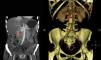

We report the case of a 41-year-old female patient diagnosed in childhood with congenital heart disease consisting of single double-chambered left ventricle with l-malposition of the great vessels and severe pulmonary hypertension in the Eisenmenger situation, with significant cyanosis and compensatory erythrocytosis, treated with sildenafil and bosentan. The diagnosis was made at five months of age and cardiac reconstruction surgery was rejected. The patient complained of HBP, asthenia, palpitations, and chest discomfort, and decompensated heart failure was found. Catecholamine hypersecretion was suspected, and hormone testing was performed with the following results: metanephrine level in 24h urine 215μg/24h (NV<341) and normetanephrine level 2491μg/24h (NV<444). An imaging study consisting of abdominal CT showed a retroperitoneal mass 3cm×2cm in size with a high contrast uptake in the interaortocaval space consistent with PG (Fig. 1). Adrenal gland scintigraphy with iodine-123MIBG and merging with CT images showed an area with pathological radiotracer uptake at the interaortocaval space coinciding with the lesion visualized by CT and consistent with the clinically suspected diagnosis. No distant lesions were shown. A molecular study was performed by sequencing encoding exons and exon–intron binding regions of genes: SDHD, SDHC, SDHB, VHL, SDHAF2, MAX, and TMEM127. No changes were found. After adequate alpha blockade with doxazosin, and under close cardiological monitoring, the patient underwent surgery. Histological examination of the surgical specimen revealed PG. No capsular or lymphovascular invasion was found. Immunohistochemistry revealed intense and diffuse expression for chromogranin, synaptophysin, and S100 staining in sustentacular areas; Ki-67 proliferation index: 1%. After surgery, urinary normetanephrine level was within the reference range, BP normalized, and there was an evident clinical improvement.